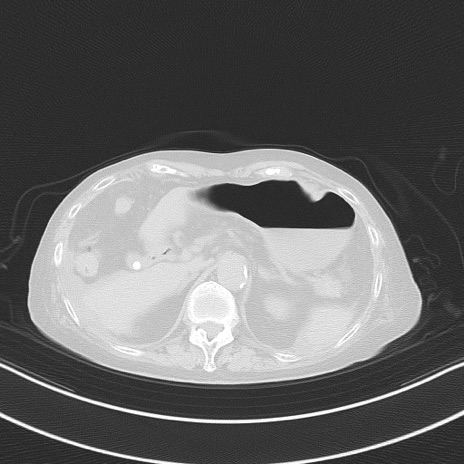

症例40(横断像)他院1日前

横断像